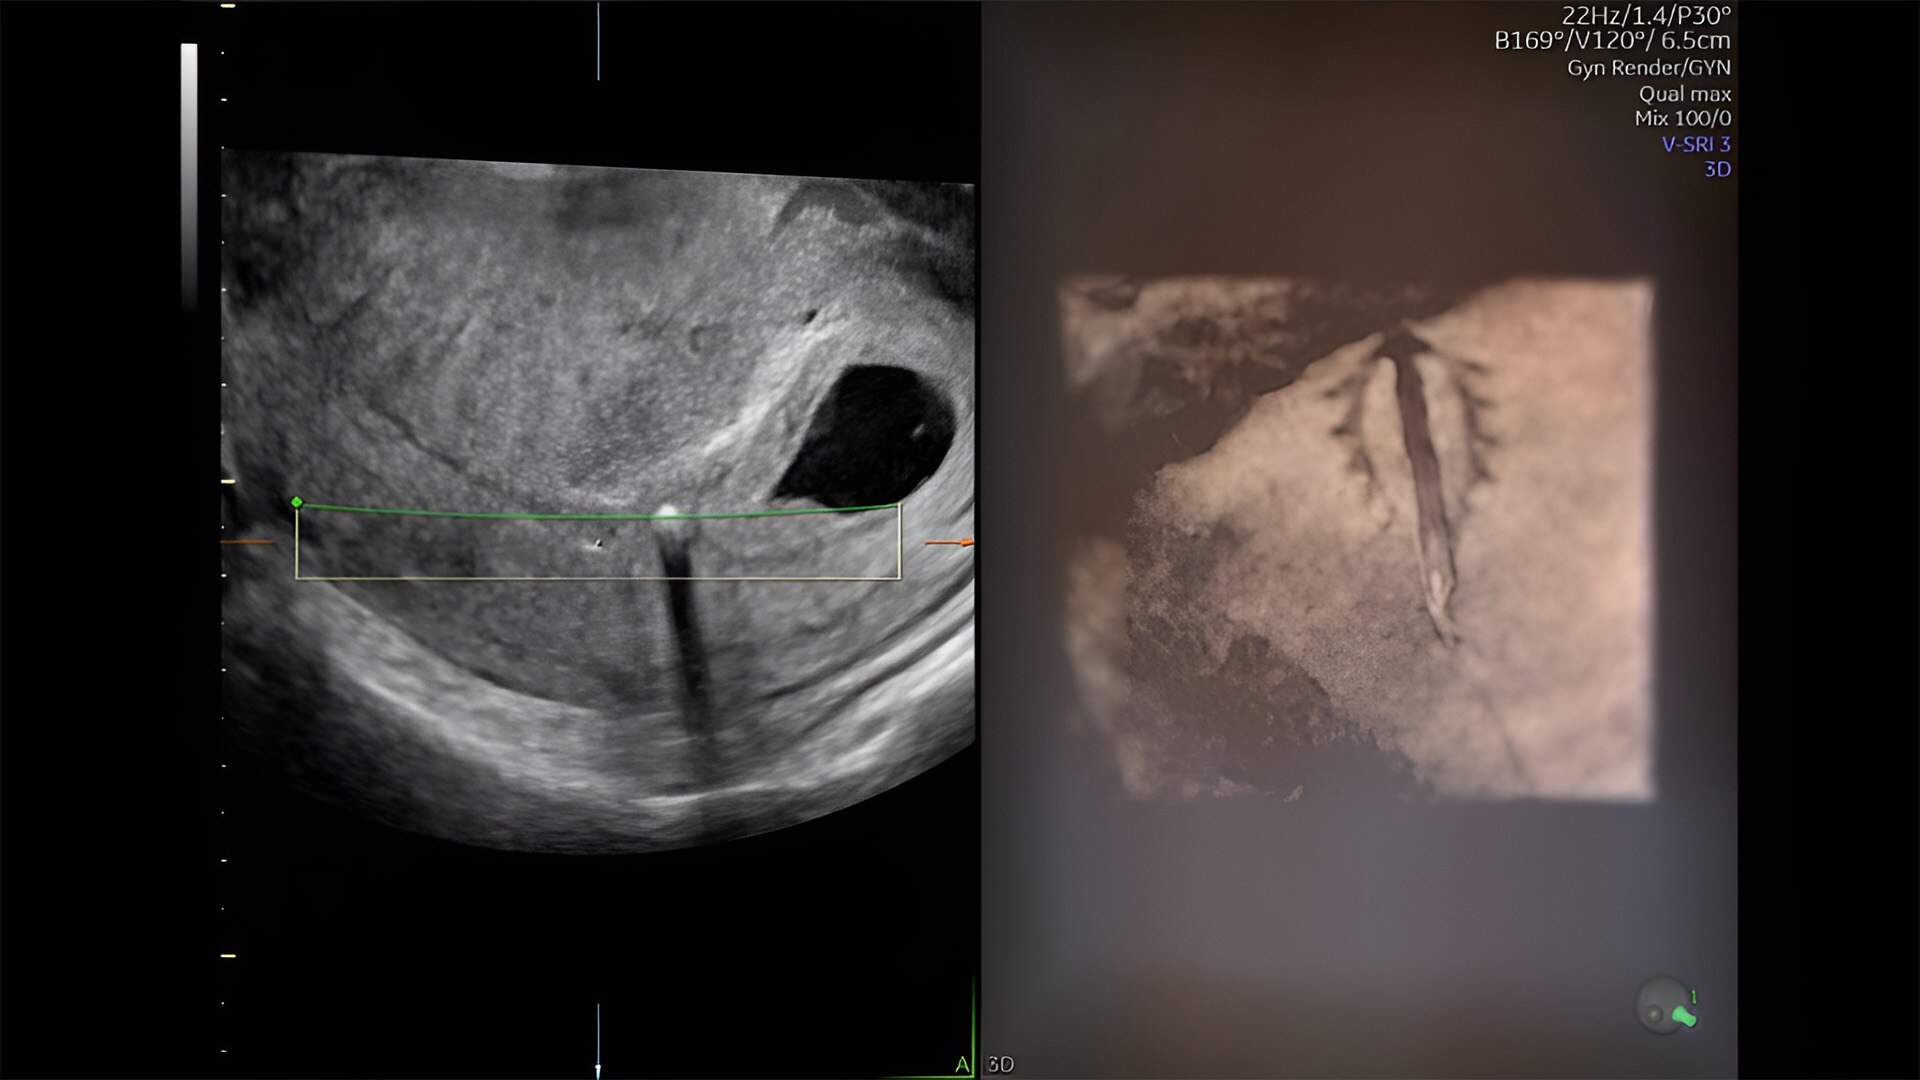

Pelvic health

Offer patient answers faster with Ai-based automation tools